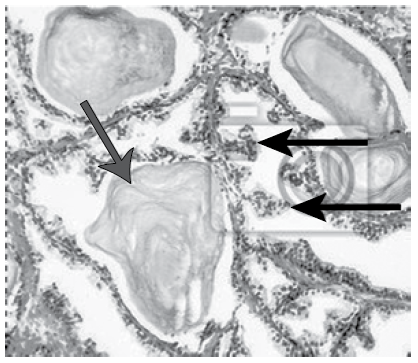

O câncer de próstata (CP) é a neoplasia mais frequente em homens e a 2a maior causa de morte entre homens no Brasil. A imagem a seguir foi realizada através de anatomopatológico de um paciente de 58 anos, etnia negra e que possui o exame nível sérico de Antígeno Prostático Específico (PSA) elevado – 5,2 ng/mL, para se necessário realizar o estadiamento na escala de Gleason.

Com base no arranjo das células conforme imagem, trata-se de

Imagem: Lâmina de anatomopatológico da próstata

(Imagem gentilmente cedida pelo Laboratório de Patologia Clínica da FMABC)